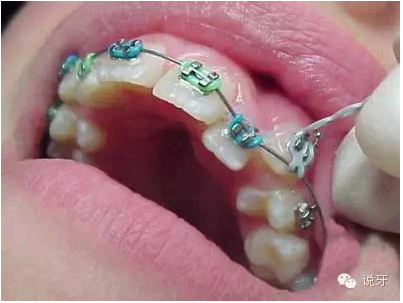

6、分牙

有的分牙是在拔牙時(shí)候同時(shí)進(jìn)行的,有的則是在拔牙后進(jìn)行。方法是用分牙圈套在上下左右的大牙之間,一般需要分1個(gè)禮拜左右。目的是為了使牙齒移出一點(diǎn)空隙,好在戴牙套的時(shí)候能夠放進(jìn)固定牙套的鋼圈。分牙一般來說會(huì)有點(diǎn)酸軟無力,上下牙齒碰到會(huì)有點(diǎn)痛哦。